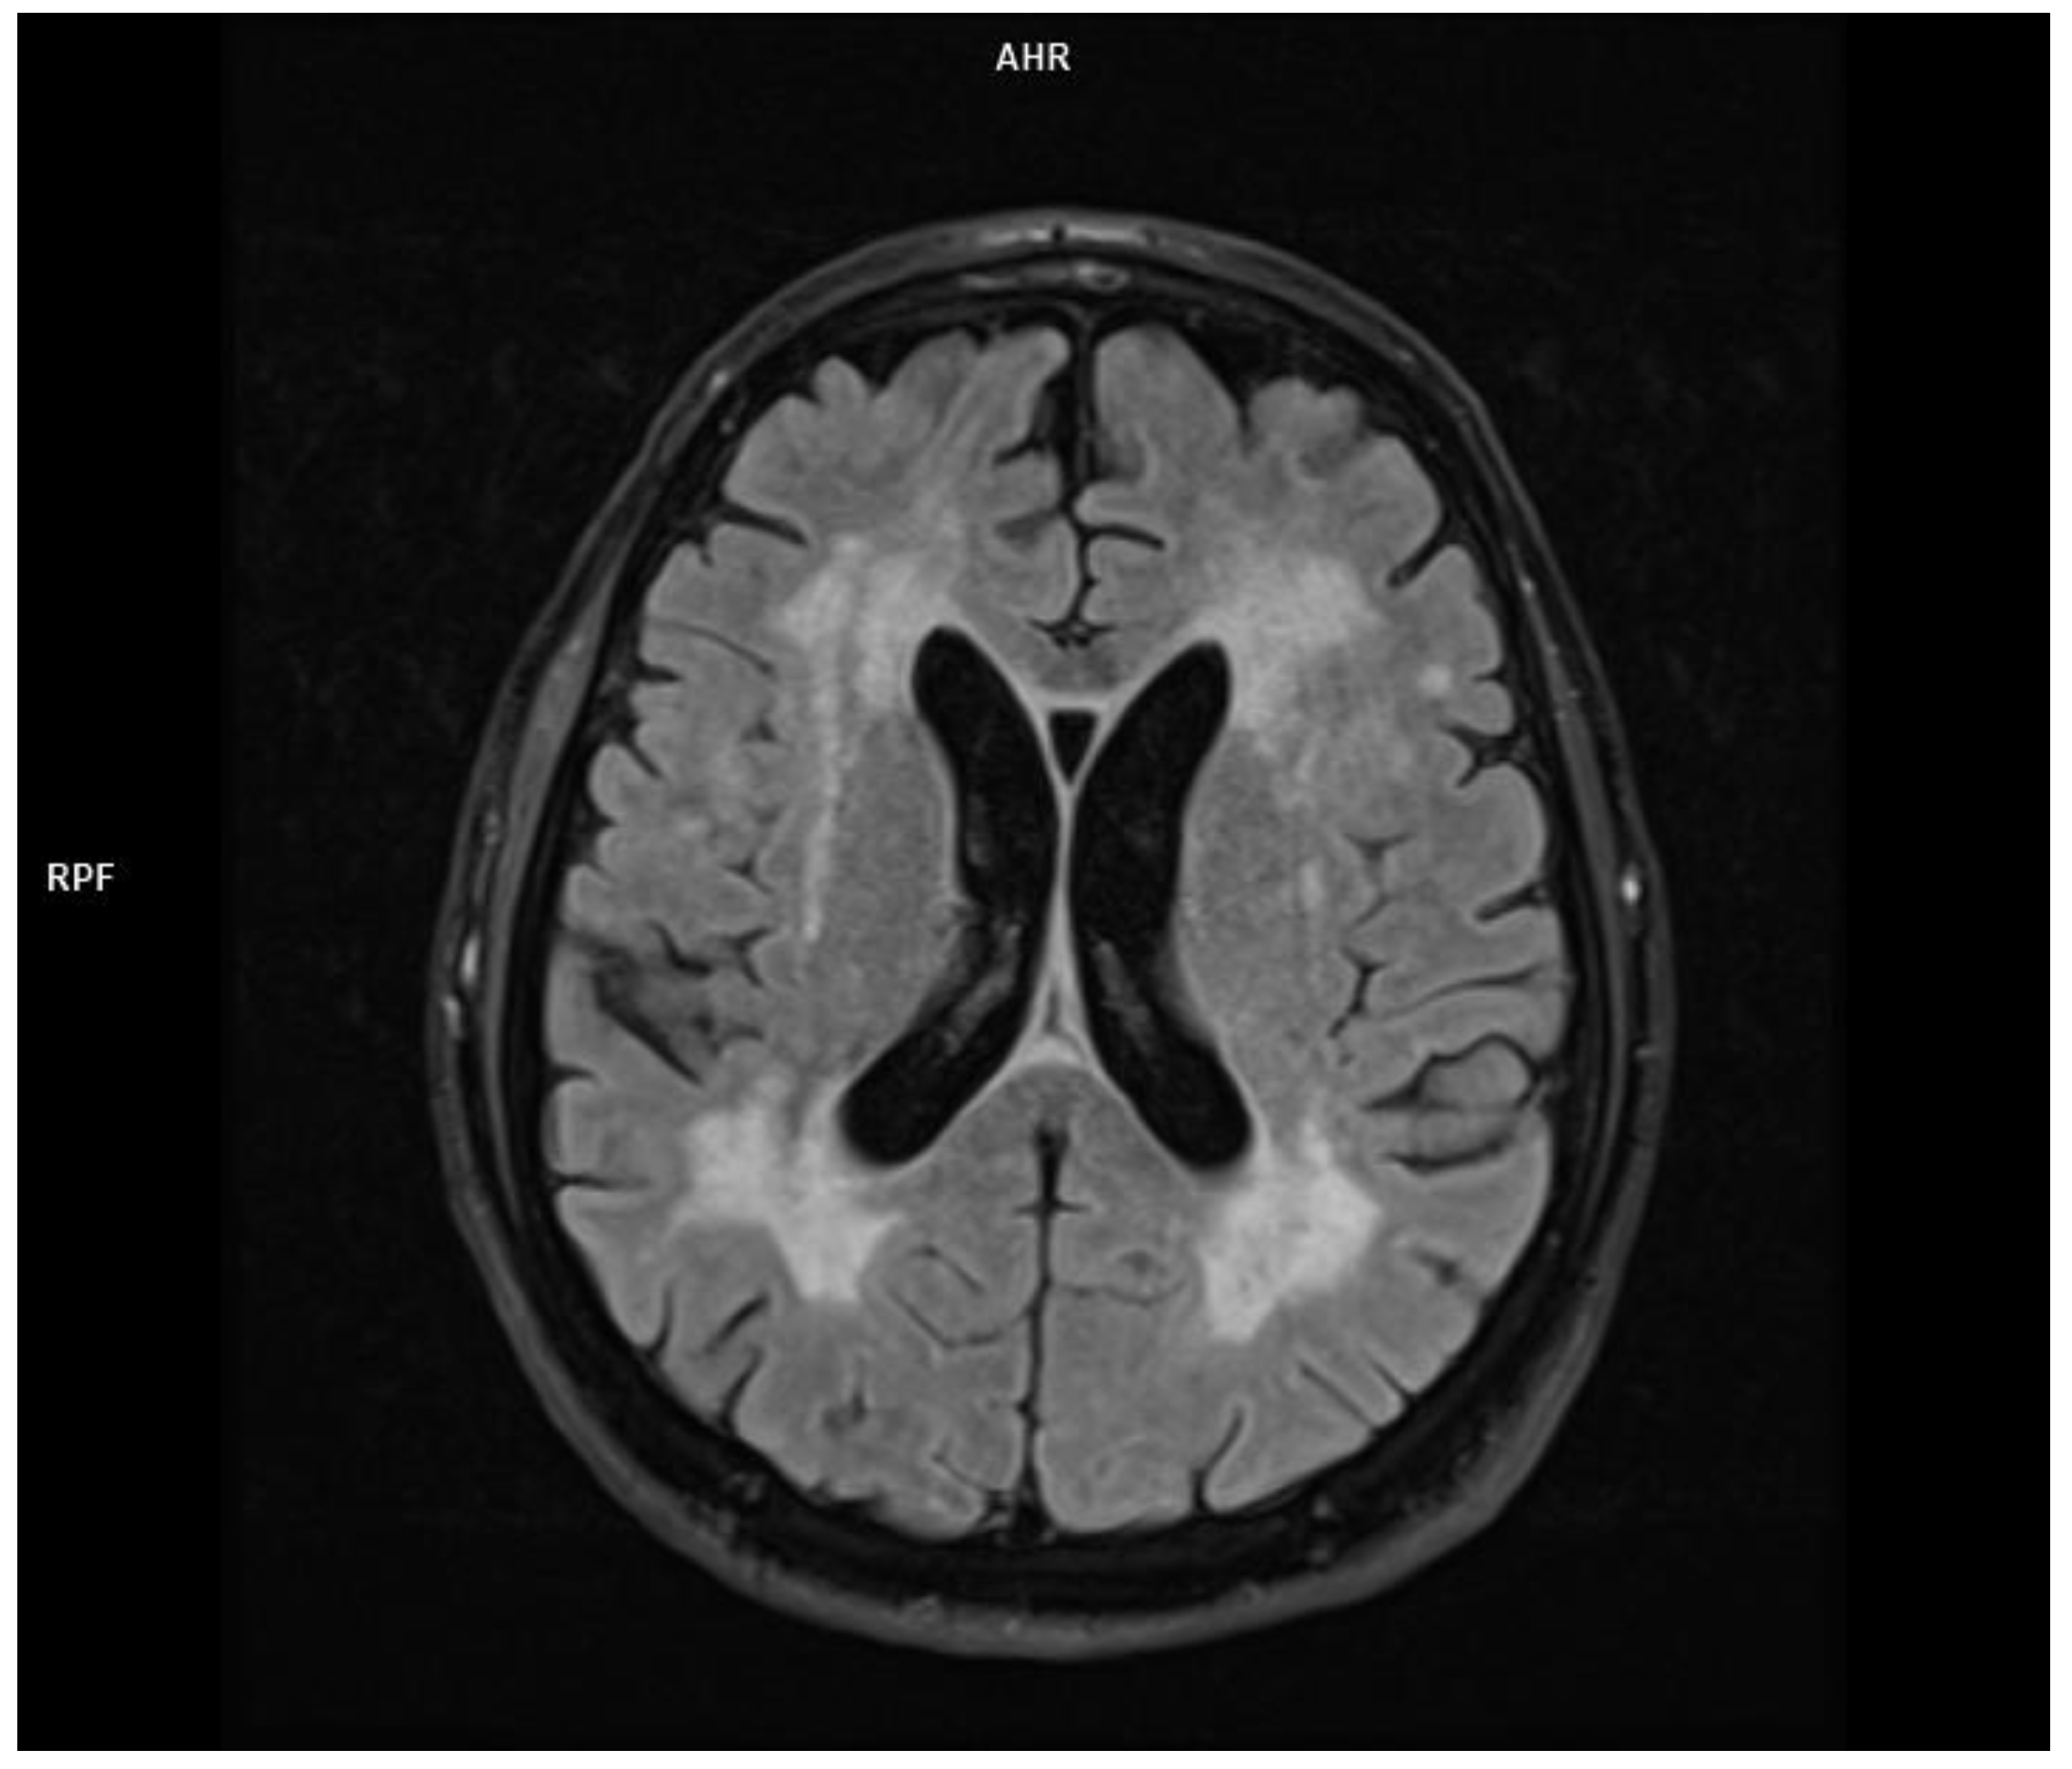

2.1. Patient 1

2.2. Patient 2

2.3. Patient 3